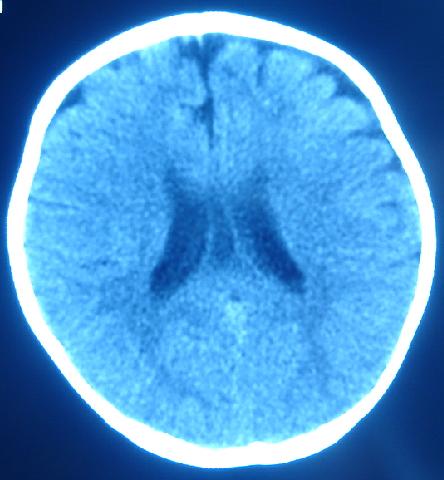

箭头指的地方是占位还是正常的直窦或正常组织?急!谢谢各位老师。

1)箭头所指:galen静脉(即大脑大静脉)。2)透明隔间腔与vergae腔并存。

1)箭头所指:galen静脉(即大脑大静脉)。2)第五脑室、第六脑室。